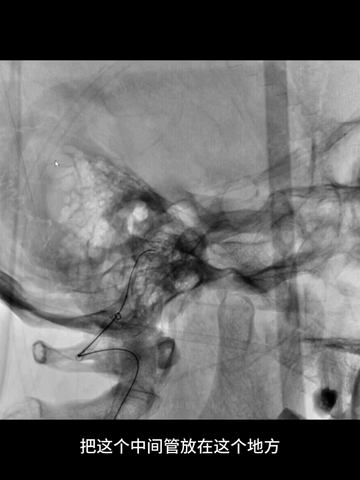

更换synchro微导丝,在微导管配合下,超选入闭塞基底动脉,并把微导管送至基底动脉远端;考虑到双侧胚胎型后交通,过程中并未尝试微导丝超选大脑后动脉。

经微导管送入一4*20mm取栓支架(S AB),释放支架后造影示闭塞再通,支架头端恰好位于基底动脉远端。

考虑到双胚胎后交通,基底动脉管径一般比较小,故回收取栓支架时6F中间管只是行至基底动脉近端,未敢深入其中。

取栓后造影示:基底动脉再通,如之前预判,其管径确实细小;同时造影剂逆流至左椎动脉V4段,显示其管径明显纤细。

中间管回撤至右V1开口处造影示:V1曲折处未见损伤征象。